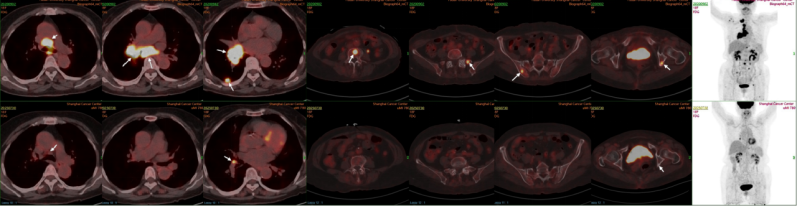

原发灶胸部CT结果对比图(基线、2周期后、4周期后、6周期后)

2、患者2025-07-30复查PET/CT:对比前片:右下肺MT治疗后,右肺病灶较前退缩,仅局部FDG代谢增高,密切随访;右侧肺门、纵隔、锁骨上转移淋巴结较前明显退缩,右肺内转移灶较前消退,全身多发骨转移较前好转,右侧胸膜转移较前消退,均未见FDG代谢增高。疗效评估为持续PR。

image.png

PET-CT结果对比图(基线、2025-07-30)